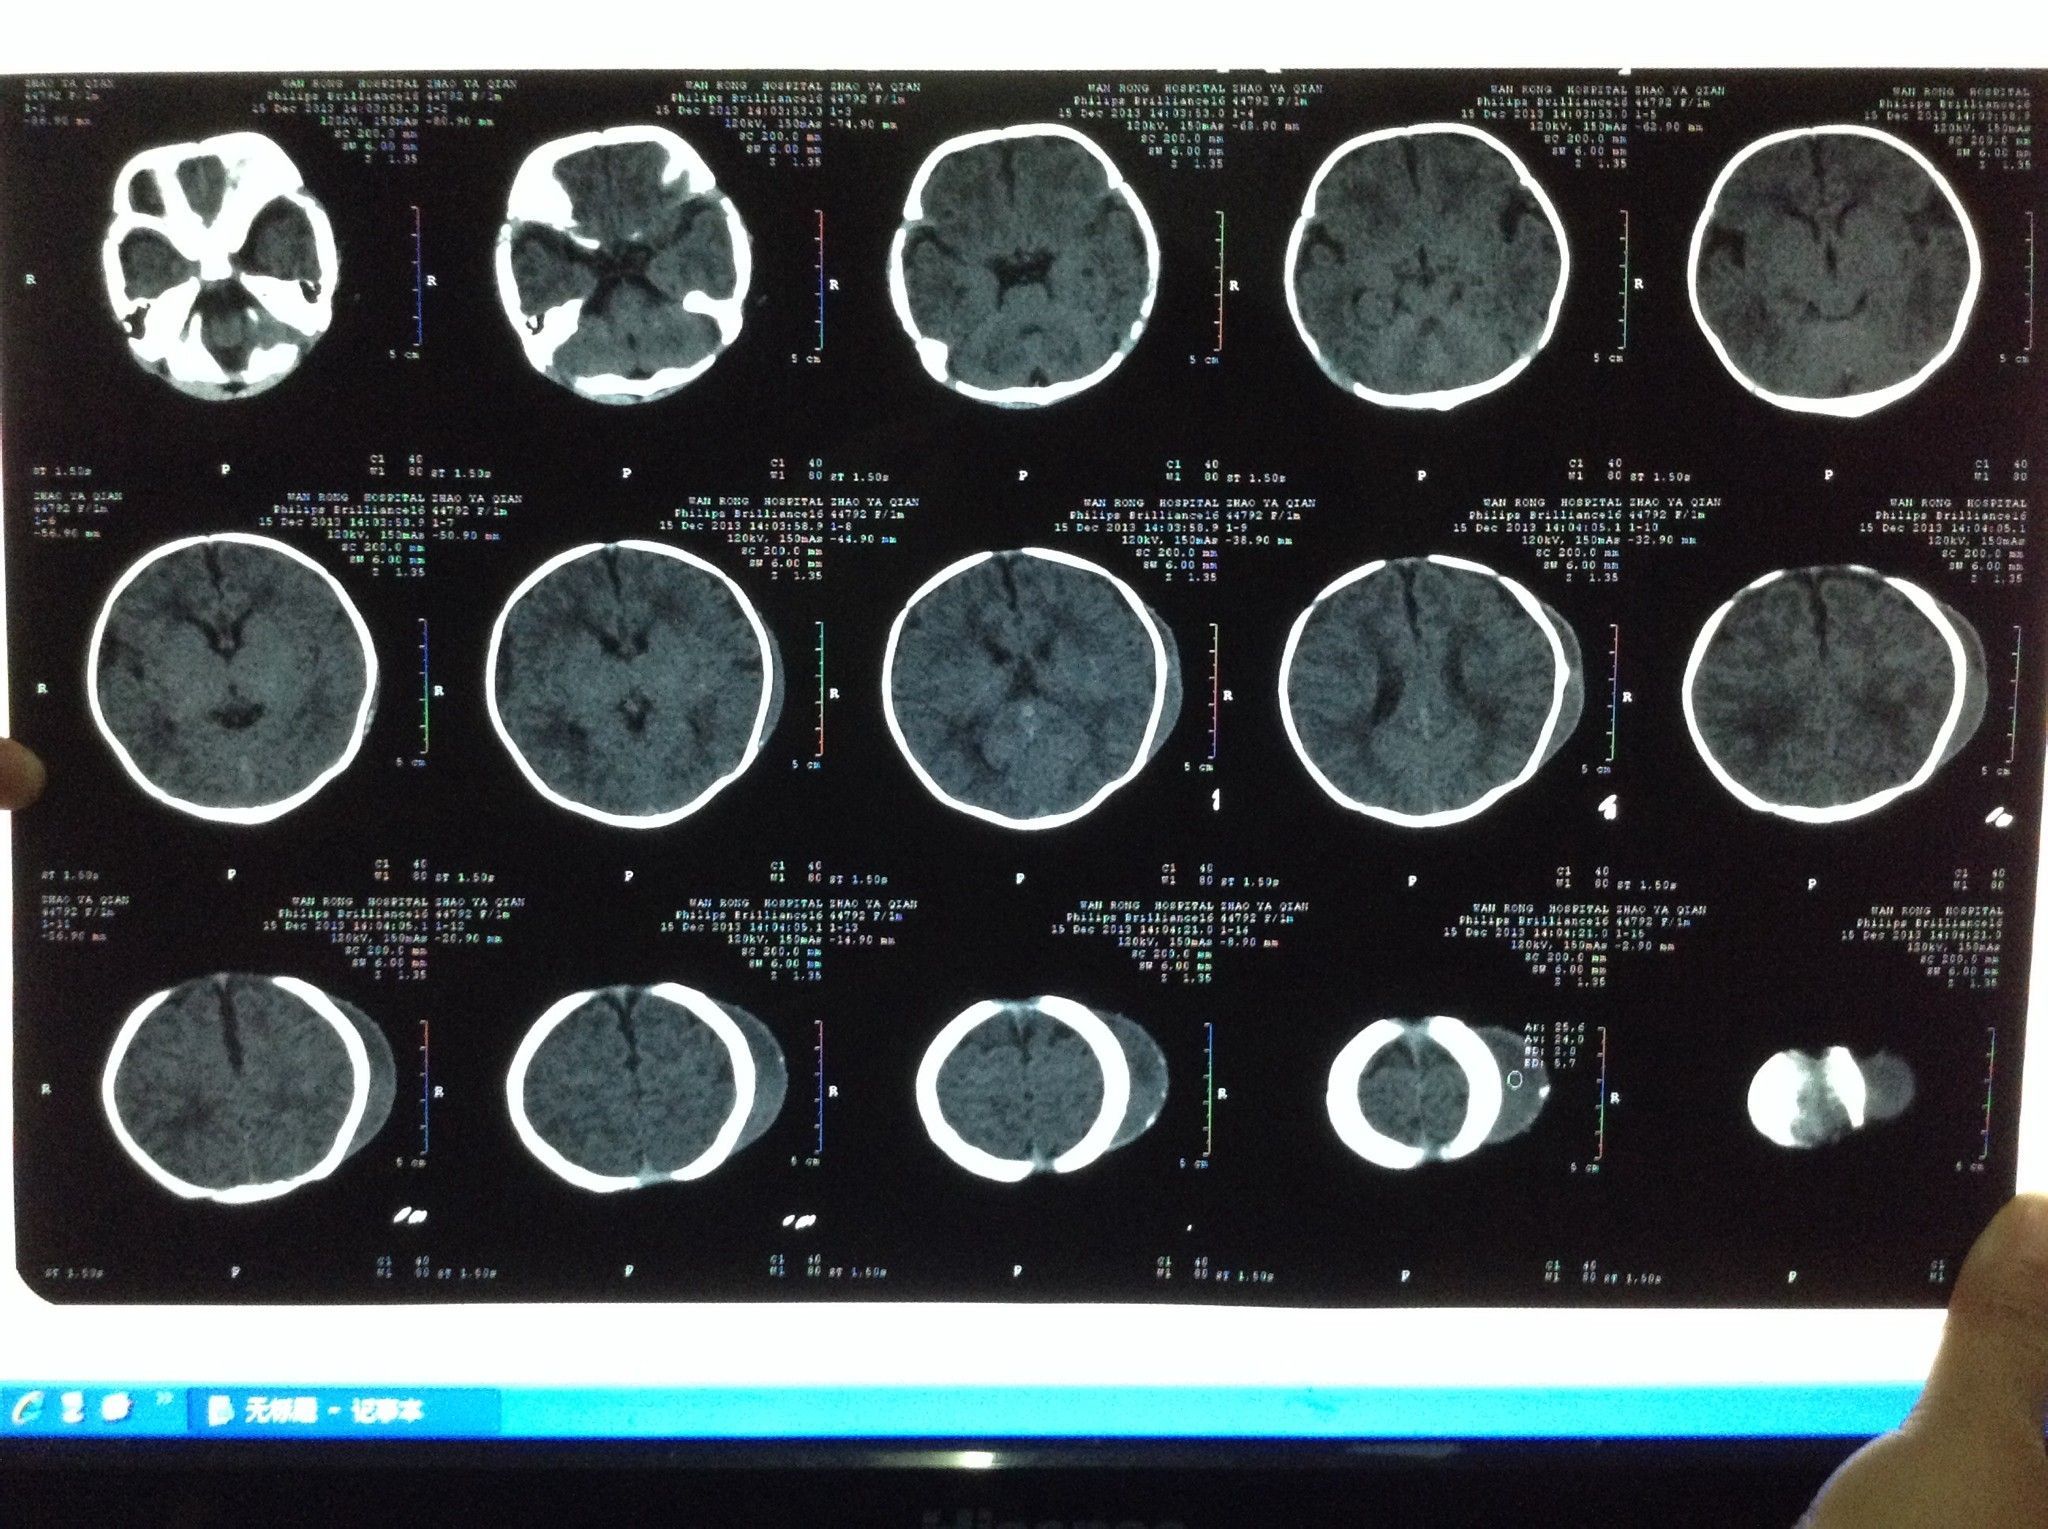

一个月新生儿头皮血肿,今天做了CT,确认是头皮血肿,头部左侧,鼓包一圈稍微有点硬,鼓包中间有一处硬 了,其余地方较软,医生说要抽,我考虑了一下,请问是用什么抽呢,抽后如何处理,如何护理,需要抽吗,一个月了,没有减小,是不是不会被吸收了?麻烦医生告知我,该怎么办,请医生看看图,是否要抽,不抽会不会变成硬的 点击展开 匿名用户 2013-12-15 18:25 为您推荐: 其他回答 现在头皮血肿我们一般不抽,可以让他吸收看看,宝宝太小。 杨冰海_vW1S 2013-12-15 18:27 相关问题 新生儿头皮血肿怎么回事?会消下去吗? 宝宝两个星期了,头鼓成这样到底要不要去拍ct啊,拍头部ct 新生儿出生时受产道挤压头部出现血肿和水肿,需要做脑CT吗?

了,其余地方较软,医生说要抽,我考虑了一下,请问是用什么抽呢,抽后如何处理,如何护理,需要抽吗,一个月了,没有减小,是不是不会被吸收了?麻烦医生告知我,该怎么办,请医生看看图,是否要抽,不抽会不会变成硬的